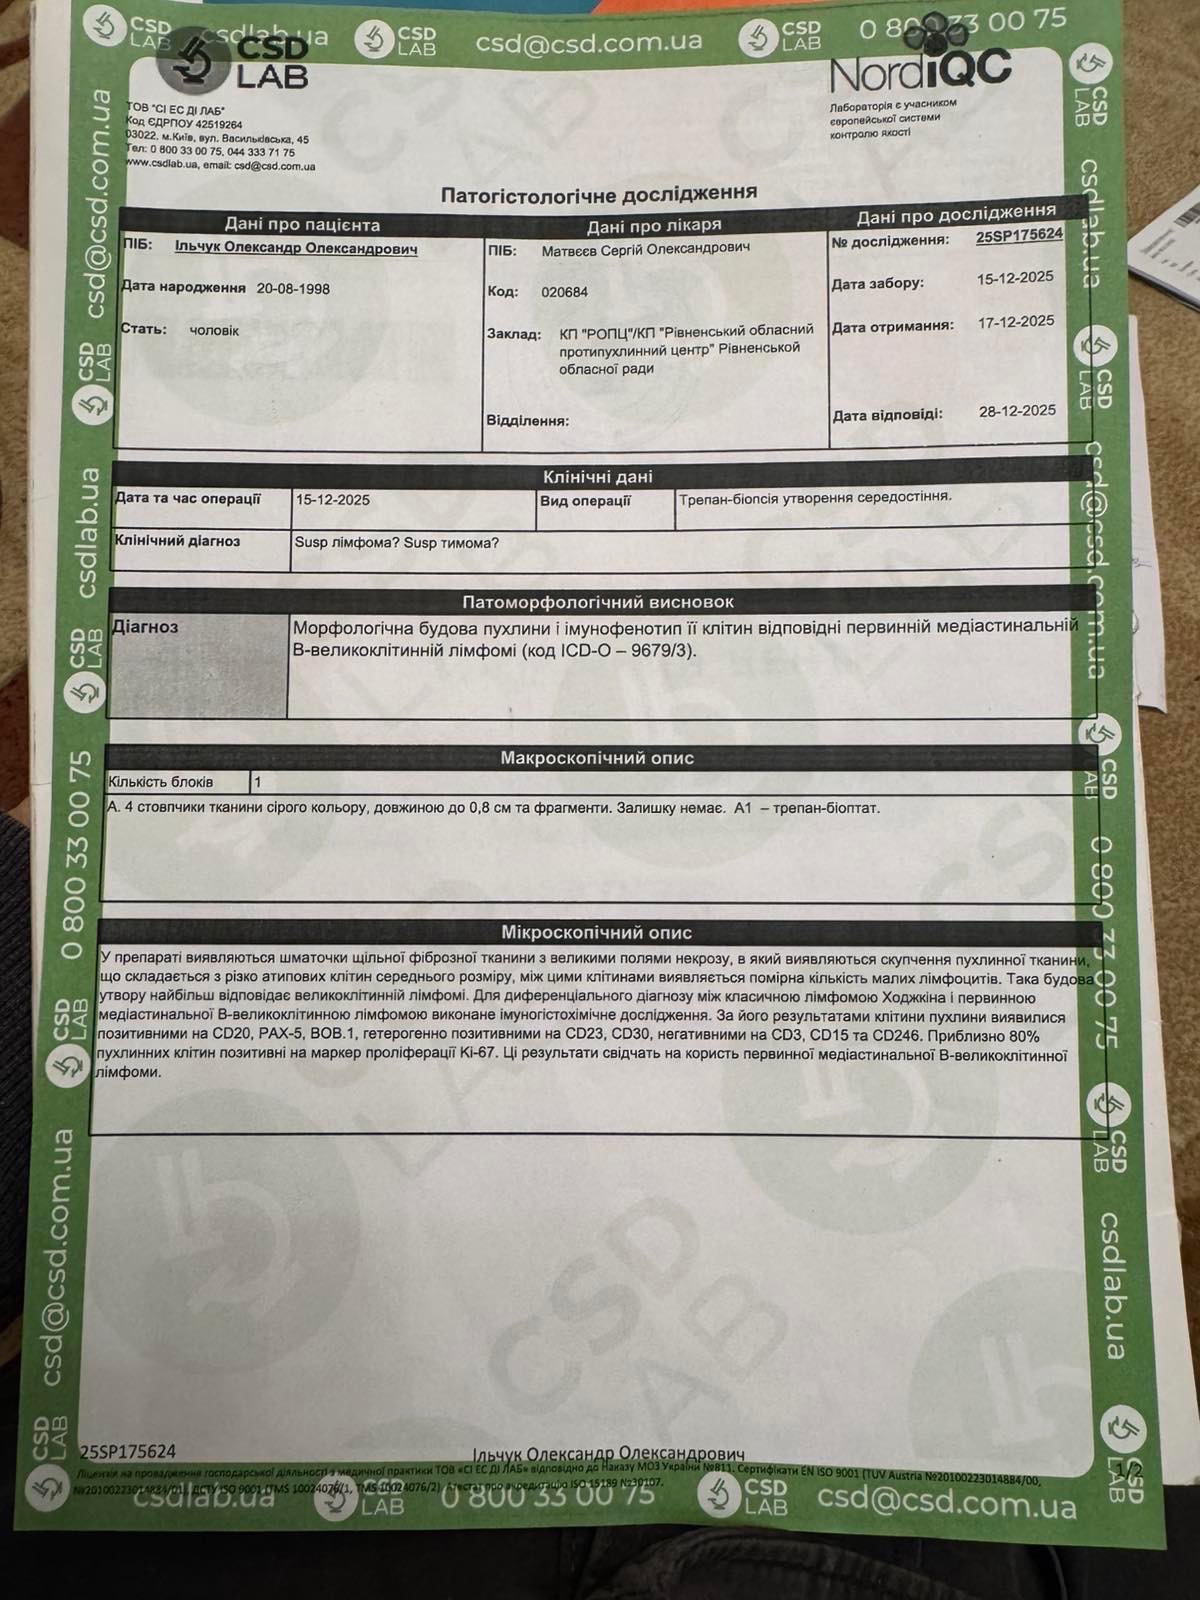

Oleksandr was diagnosed with Primary Mediastinal Large B-Cell Lymphoma, an aggressive but treatable form of cancer. The diagnosis came as a complete shock, especially given his young age and the fact that he was just starting a new chapter of life as a husband and soon-to-be father.

Олександру поставили діагноз — первинна медіастинальна великоклітинна В-клітинна лімфома — агресивна, але лікувальна форма раку. Цей діагноз став повним шоком, особливо з огляду на його молодий вік і те, що він лише починав новий етап життя як чоловік і майбутній батько.